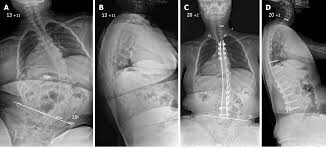

JBJS.2007から引用

治療は多くの場合に手術が行われます。

手術は他の側弯と同じで金属で背中の骨を固定します。

デュシェンヌ型の側弯の目的は背骨がまがって座れないことを治すことです。

角度よりも座位の保持ができなくなれば手術を検討するタイミングです。